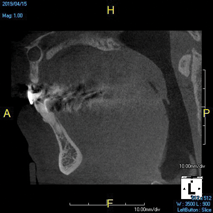

(11.) A pathosis apical to the maxillary central incisors was initially not diagnosed after evaluating the periapical film; however, the CBCT image revealed its presence. Only using the CBCT image could it be determined that the lesion was not odontogenic in origin and that it did not involve the nasopalatine foramen. This diagnosis was supported by a referral to an oral and maxillofacial radiologist.

Figure 11

(12.) A pathosis apical to the maxillary central incisors was initially not diagnosed after evaluating the periapical film; however, the CBCT image revealed its presence. Only using the CBCT image could it be determined that the lesion was not odontogenic in origin and that it did not involve the nasopalatine foramen. This diagnosis was supported by a referral to an oral and maxillofacial radiologist.

Figure 12